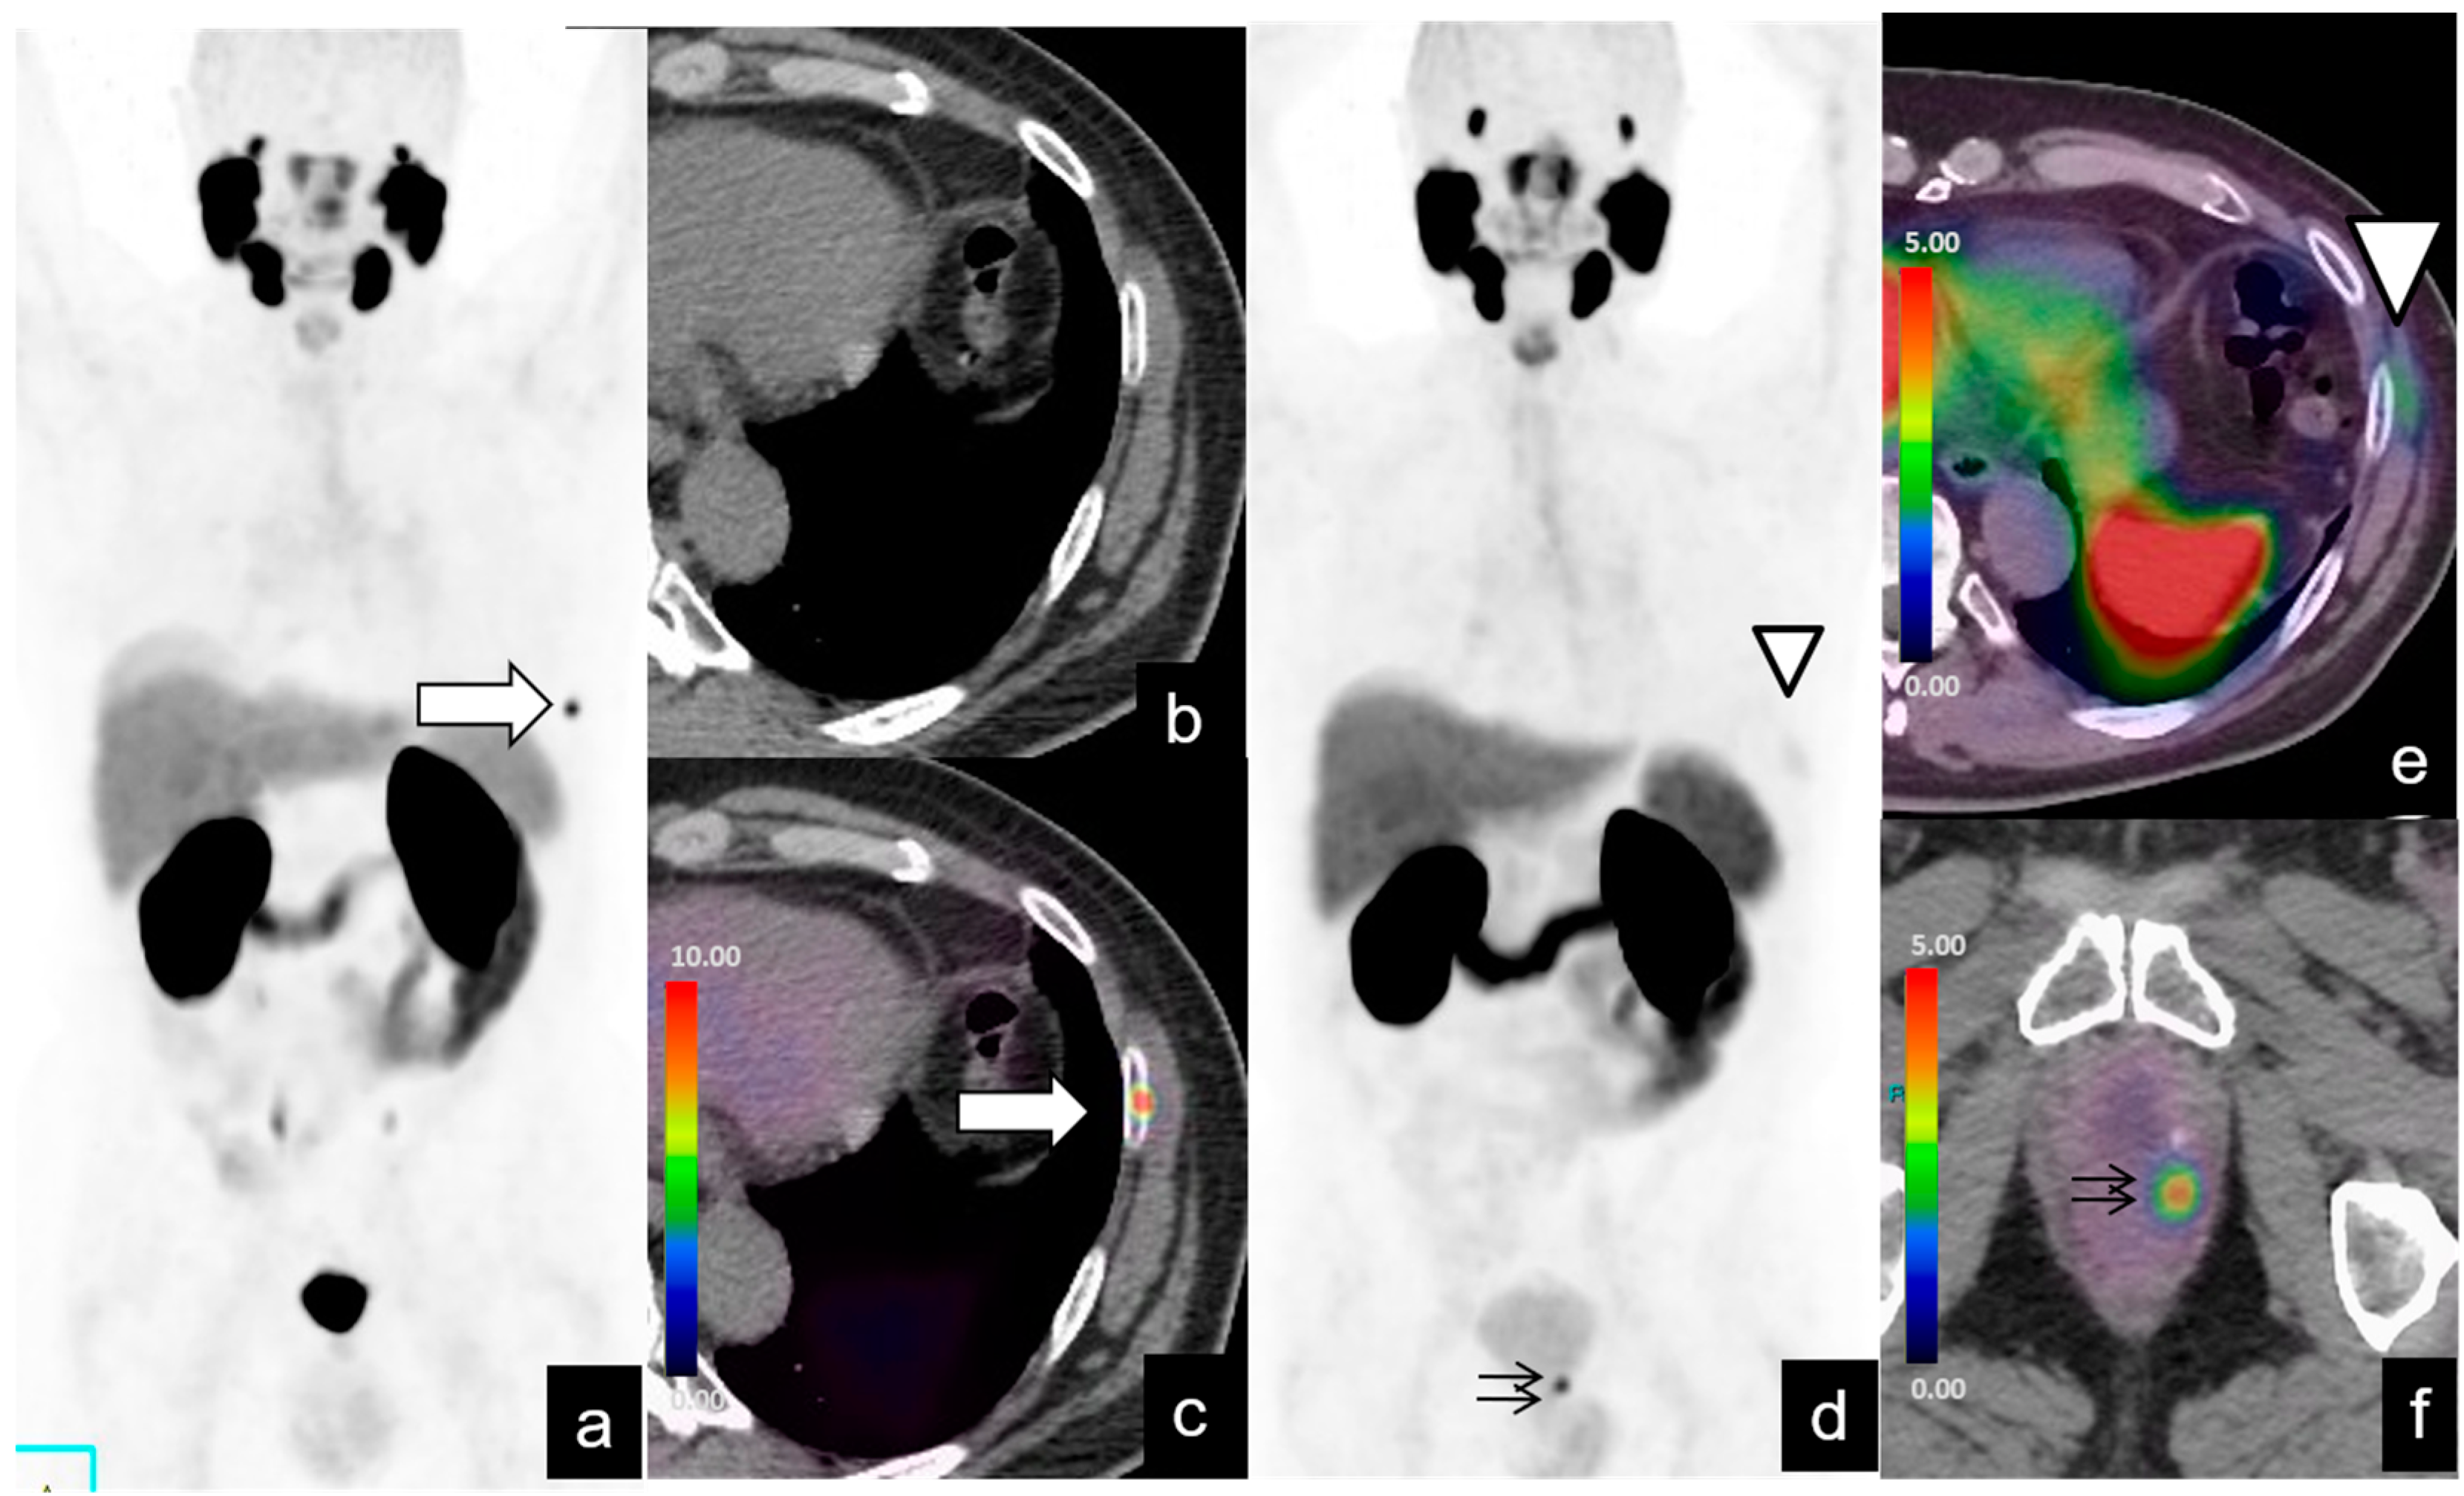

| Region | No. of Patients (%) | SUVmax Median | SUVmax Range | Size (mm) Median | Size (mm) Range |

|---|---|---|---|---|---|

| Local recurrence | 42/128 (32%) | 12 | 2.1–46 | 9.6 | 3–53 |

| Lymph-node metastases | |||||

| Abdominopelvic | 39/128 (30%) | 24 | 1–73 | 7.3 | 2–19 |

| Supradiaphragmatic | 4/128 (3%) | 27.2 | 3–60 | 18.5 | 15–22 |

| Bone metastases | 20/128 (15%) | 19 | 1.9–70 | ||

| Other (e.g., lung, liver) metastases | 5/128 (3%) | 14.6 | 2.5–17 |